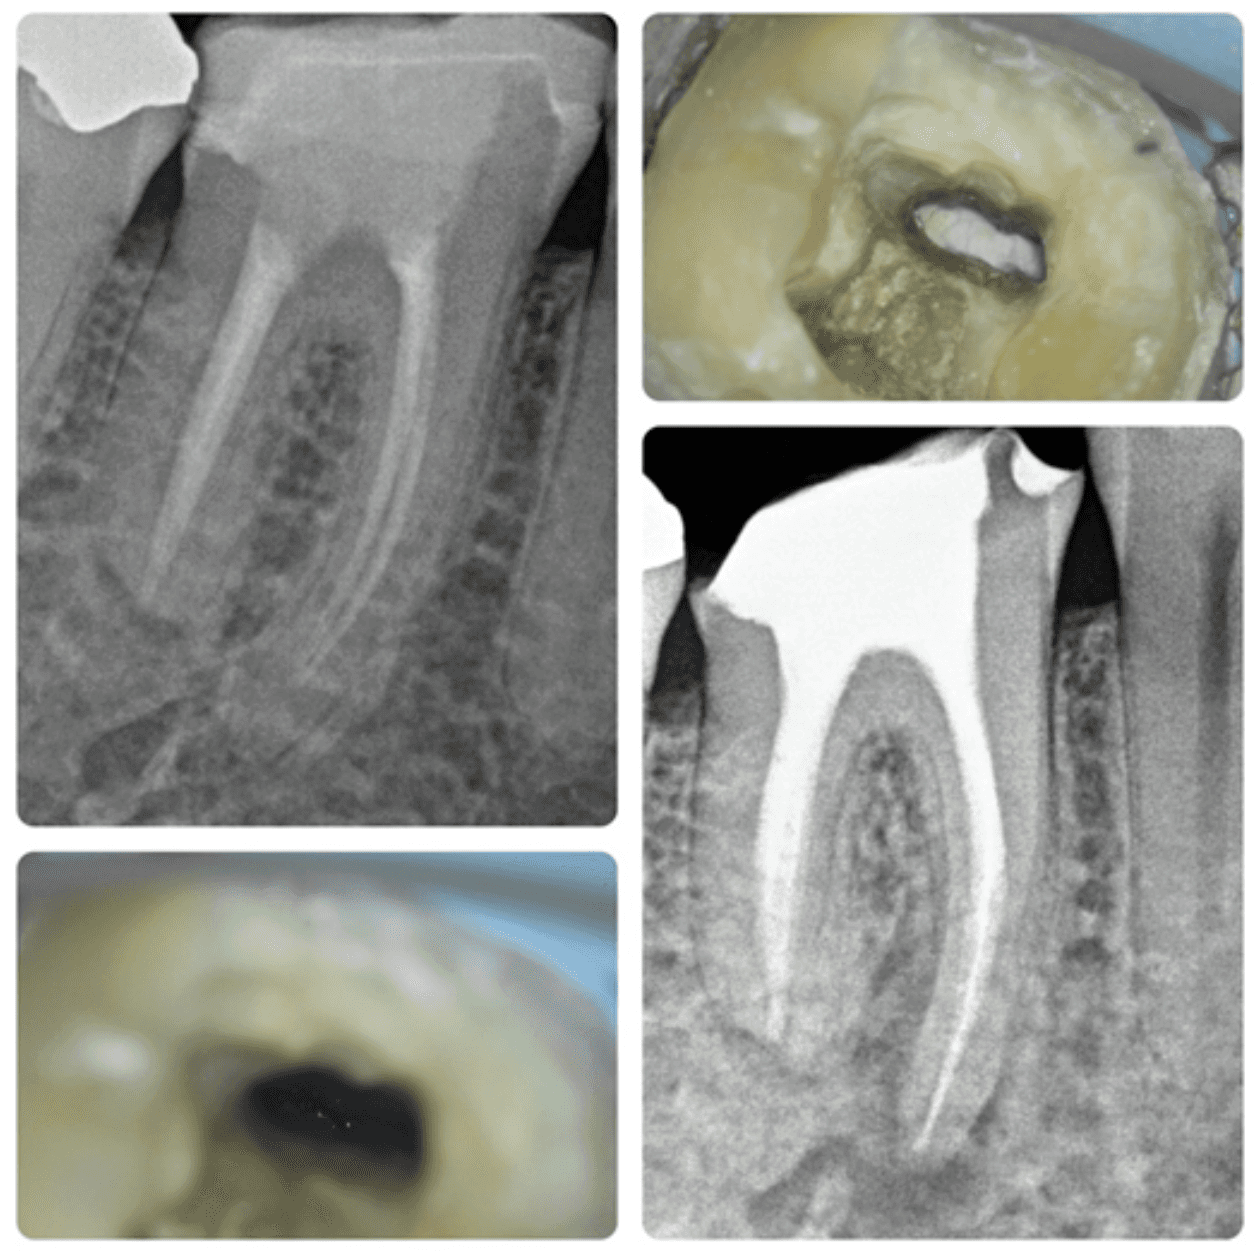

KREENA'S CASES